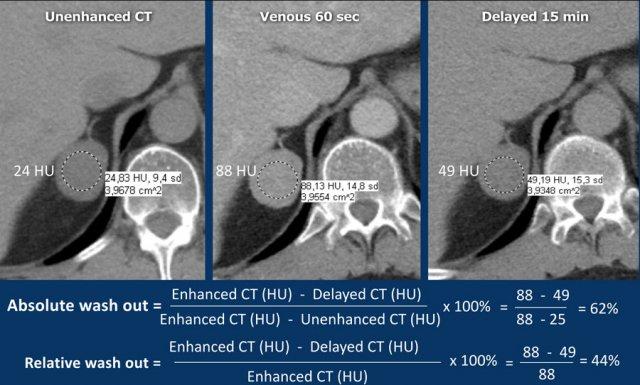

Độ thải thuốc tuyệt đối

Quy trình CT đánh giá độ thải thuốc tuyến thượng thận chuyên biệt bao gồm: pha không tiêm thuốc, pha tiêm thuốc cản quang với thì chụp muộn 60-90 giây, và pha chụp muộn tại thời điểm 15 phút.

Vùng quan tâm (ROI) cần bao phủ ít nhất 2/3 diện tích tổn thương để đảm bảo tính đại diện trong đánh giá.

Độ thải thuốc tuyệt đối ⩾ 60% là bằng chứng xác định u tuyến [5,6,8].

Độ thải thuốc tương đối

Nếu tổn thương tuyến thượng thận được phát hiện trên pha tiêm thuốc cản quang trong khi bệnh nhân vẫn còn trên bàn chụp, có thể thực hiện thêm một lần chụp tuyến thượng thận tại thời điểm 15 phút sau khi tiêm thuốc và tính toán độ thải thuốc tương đối.

Độ thải thuốc tương đối ⩾ 40% là bằng chứng xác định u tuyến [5,6,8].

Các hình ảnh cho thấy một tổn thương chưa xác định trên CT không tiêm thuốc cản quang (tỷ trọng 24 HU).

Độ thải thuốc tuyệt đối ở bệnh nhân này là 62%.

Điều này có nghĩa là tổn thương là u tuyến nghèo lipid.